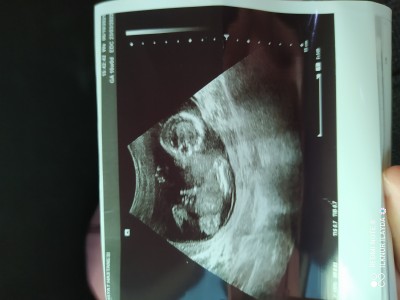

Cinsiyet tahmini alablrmym ☺️ bakalm tutucak mı

Cinsiyetmz ne sizce teyzeleri ♥️

Elleriyle aha bak bak belli diyor

Ben kıza benzettim

Kiza benziyor bacağı açık pipisi yok sanki ama allah kerim rabbim sağlıklı hayırlı evlat olsun

Erkek.........

Erkeklerin iskelet yapısı daha erken oluşuyor diye biliyorum. Gözlemlediğim kadarıyla da böyle erken haftalarda net belli olunca erkek, çok anlaşılmayınca kız çıkıyor :)

baby girl bu yaaa

erkek diyen olmus ama pipi yok orda suan bende kiz bebege hamileyim benzettim ☺❣